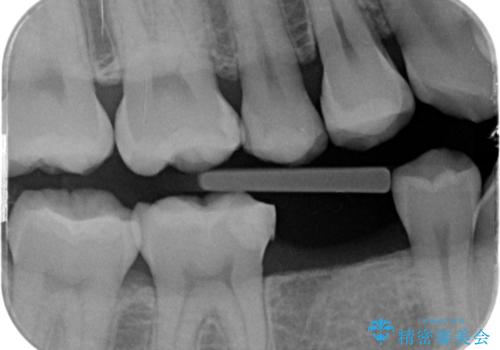

虫歯の再発リスクが高い樹脂修復部分をe-maxインレーに

- 歯と歯の間に古い樹脂の治療がされていて虫歯の再発のリスクが高まるためにe-maxインレー(セラミック)治療を行いました。

適合の良い詰め物が入りました。

セラミックは適合がよく虫歯の再発のリスクが低くなります。